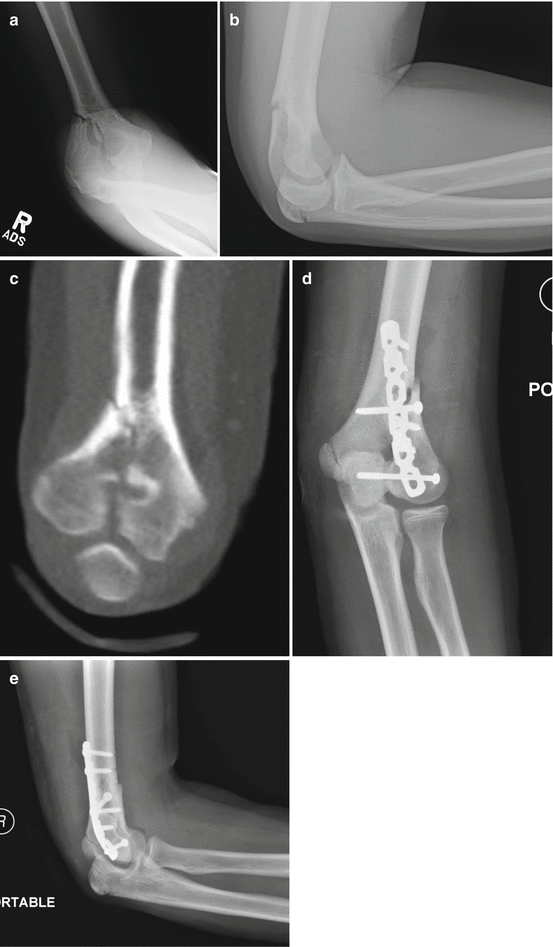

S40S49 Injuries to the shoulder and upper arm ;. Comminuted T condylar fracture of the left distal humerus is noted with intraarticular extension Posterior displacement of the distal fragment is seen in the sagittal plane;. By definition, Tcondylar fractures are intraarticular, distal humerus fractures characterized by a central intercondylar split and extension of the fracture line proximally through both the medial and lateral columns Tcondylar fractures in children are rare elbow fractures and are, perhaps, the most challenging to manage.

Tcondylar fracture is a type of distal humerus fracture Tcondylar fracture in children is rare, with reported incidence of less than 1% of Tcondylar fractures The mean reported age of. Although fractures of the elbow are extremely common in pediatric patients, the Ttype distal humerus fracture is rare and offers unique challenges The mechanism of injury may be similar to the adult counterpart and is usually caused by a fall onto a flexed elbow or from a direct blow Diagnosing these injuries may be difficult. Tcondylar fractures of the distal humerus are very rare in children High degree of suspicion and then further imaging are needed for these types of injuries to be detected Tcondylar fractures can have a high chance of complications Parents should be warned about the likelihood of an unsatisfactory outcome.

Pediatric Tcondylar humerus fractures requiring an open approach may benefit from less invasive approaches such as the triceps split approach where the fracture pattern allows Younger children are more amenable to less invasive means of fracture reduction and fixation If an articular reduction is required, the aggregated literature suggests that the Morrey slide offers equivalent results to the olecranon osteotomy but with fewer approachrelated complications. Blakey CM, Biant LC, Birch R Ischaemia and the of elbow fracture in children analysis of 355 pink, pulseless hand complicating supracondylar fractures, with special reference to supracondylar fractures of the humerus in childhood longterm humerus fractures. With mild lateral/valgus displacement and rotation is noted in the coronal plane No radial or ulnar fracture is notedSoft tissue swelling is noted around the elbow.

Coronal shear fractures ;. ORIF Fractures – Distal Humerus, TCondylar, Radial Head, Olecranon The Open Reduction Internal Fixation (ORIF) of the distal humerus is an operation that fixes fractures in the humerus that are generally difficult to secure with a cast or splint (external fixation).